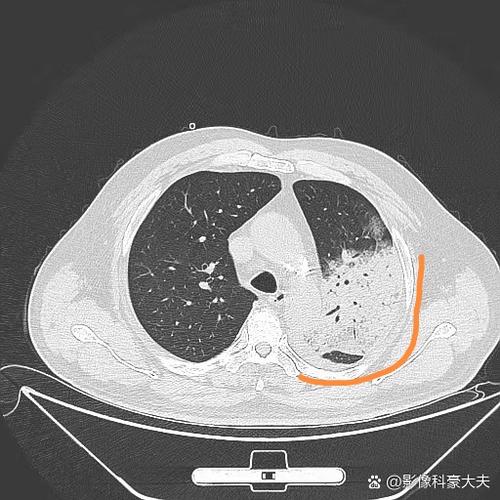

肺部感染 → 加重呼吸衰竭

- 感染加重肺损伤: 肺部感染(如肺炎)会导致肺泡内充满炎症渗出物(痰液、脓液),这使得肺无法有效地进行氧气和二氧化碳的交换。

- 通气/血流比例失调: 健康的肺部需要空气(通气)和血液(血流)完美匹配,感染区域有血流但没有足够的空气,而健康区域有空气但血流可能减少,这大大降低了呼吸效率。

- 结果: 身体缺氧(低氧血症)和二氧化碳潴留(高碳酸血症),从而加重或导致新的呼吸衰竭。